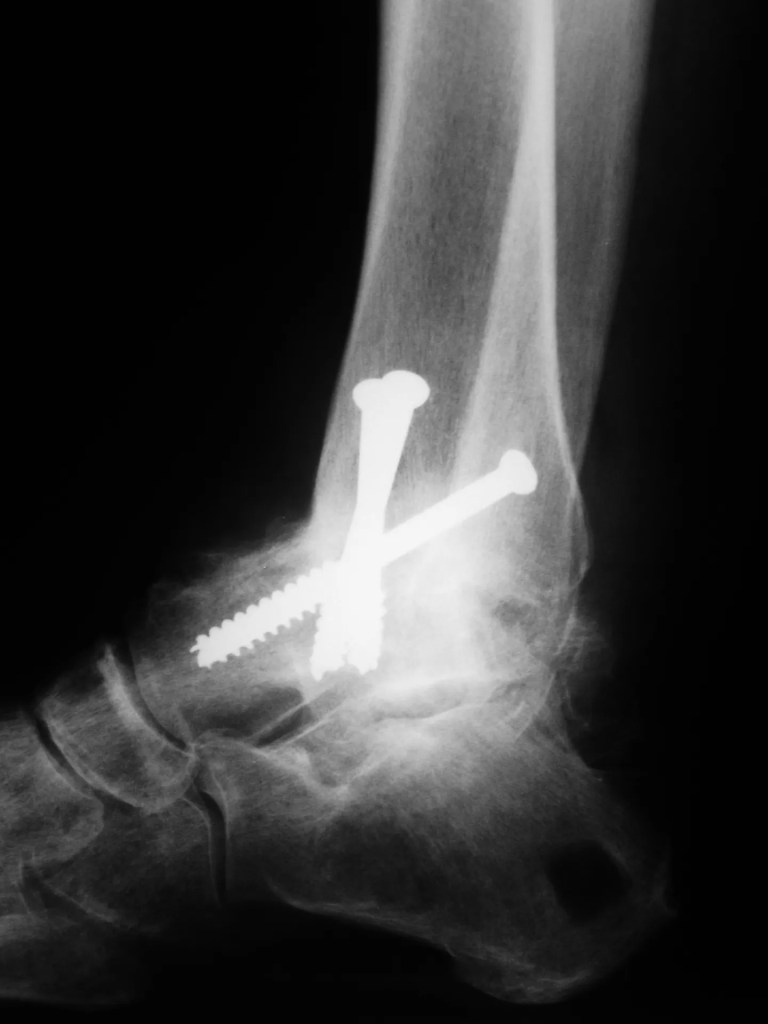

I just knew it, I knew the time had finally come when I would have to have an ankle replacement. It was an accident over 27 years ago, my ankle was smashed and now it was making its undesirable presence felt. Perhaps it was stupidity or the bloody-mindedness of a marathon runner, I am unsure, but I chose to pretend I was a hero. Pinned ankle or not – I would not stop running. And why not? I was still pretty young at 35 years and I was fit. I had run an eight-hour Comrades Marathon recently and had a silver medal in my sights. And so once the plaster cast was off and I could manage without crutches, I started to run. Again.